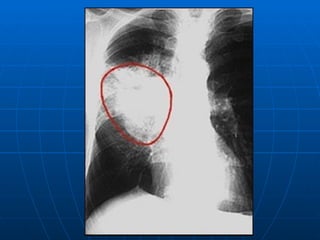

Chest radiograph of a patient with bilateral  pulmonary metastases from endometrial cancer . The mass in the right upper lobe is well circumscribed and has the radiographic appearance typical of a metastasis.

Chest radiograph ofa patient with bilateral pulmonary metastases from endometrial cancer . The mass in the right upper lobe is well circumscribed and has the radiographic appearance typical of a metastasis.